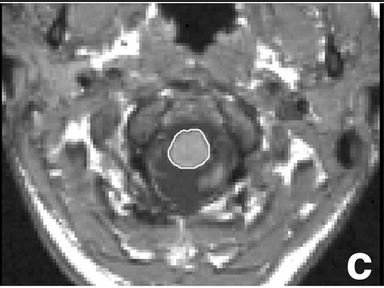

Fig1c Piaggio et al NovDue to the fact that spinal cord atrophy is not routinely assessed in routine clinical practice, despite being one of the hallmarks of amyotrophic lateral sclerosis, this study was designed to evaluate whether spinal cord cross-sectional area measured at the foramen magnum level using an MRI scan represents a meaningful measure to be added to the whole-brain volume assessment.